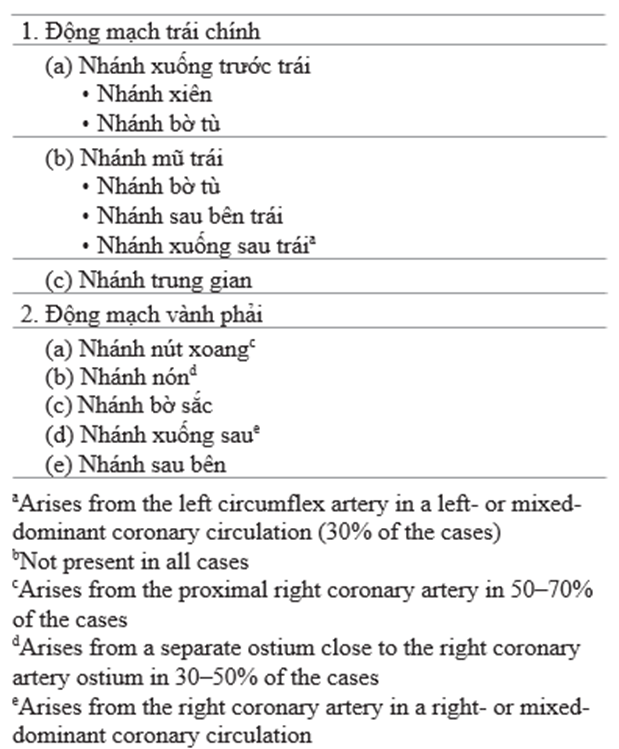

2. Có 2 động mạch thượng tâm mạc lớn: nhánh chính trái và nhánh vành phải bắt nguồn từ xoang trái và phải của xoang Valsalva ở đáy của đoạn lên động mạch chủ [2]. Động mạch chính trái chia làm nhánh xuống trước trái chính (LAD) và nhánh mũ trái (LCX). Trong 1 số trường hợp, nhánh chính trái còn chia thêm nhánh thứ 3 là nhánh trung gian. nhánh LAD và LCX chia thành nhánh xiên và nhánh bờ tù. Tuần hoàn vành nguồn gốc từ động mạch xuống sau (PDA) cấp máu cho phần sau của vách liên thất. PDA từ nhánh vành phải ở 70% bệnh nhân và nhánh mũ trái ở 15% bệnh nhân. Các trường hợp còn lại xuất phát từ cả nhánh phải và nhánh mũ [3].

Danh pháp của các đoạn khác nhau trên hệ mạch vành được mô tả bởi tổ chức Bypass Angioplasty Revascularization Investigation (BARI), và nằm ngoài phạm vi chương này [4]. Table 71.1 tóm tắt các nhánh chính của động mạch vành

Table 71.1 nhánh chính của động mạch vành (hệ thống mạch bên phải)